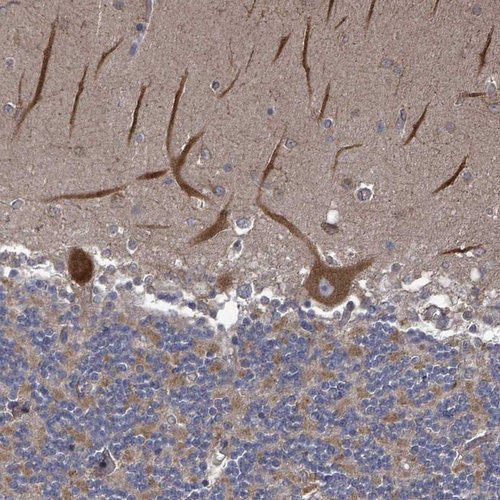

Immunohistochemical staining of human cerebellum shows moderate cytoplasmic positivity in Purkinje cells.